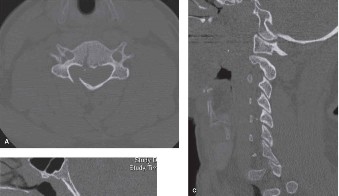

When blood cultures are negative or deemed unreliable, a CT-guided percutaneous needle biopsy of the disc space or vertebral body is the mandatory next step before committing to long-term empiric antibiotics. Empiric antibiotics should ideally be withheld in the hemodynamically stable patient until deep tissue cultures are obtained. If the initial CT-guided biopsy is non-diagnostic, a second percutaneous biopsy or an open/endoscopic incisional biopsy may be warranted.

In addition to MRI, a fine-cut computed tomography (CT) scan is essential for evaluating bony destruction. CT allows the surgeon to assess bone stock for pedicle screw purchase and to template the size of the interbody cages required for anterior column reconstruction. Upright standing radiographs (if the patient can tolerate them) or full-length supine films are necessary to evaluate global spinal alignment and regional kyphosis.